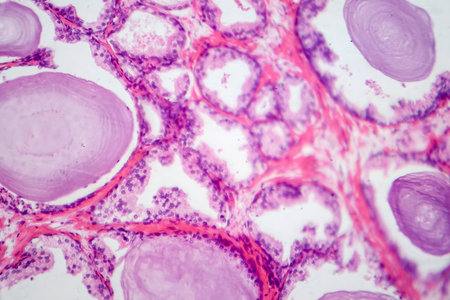

Light micrograph of teratoma, a tumor made up of several different types of tissue, such as hair, teeth, muscle, or bone. Teratoma is typically found in the ovary, testicle, or coccyx